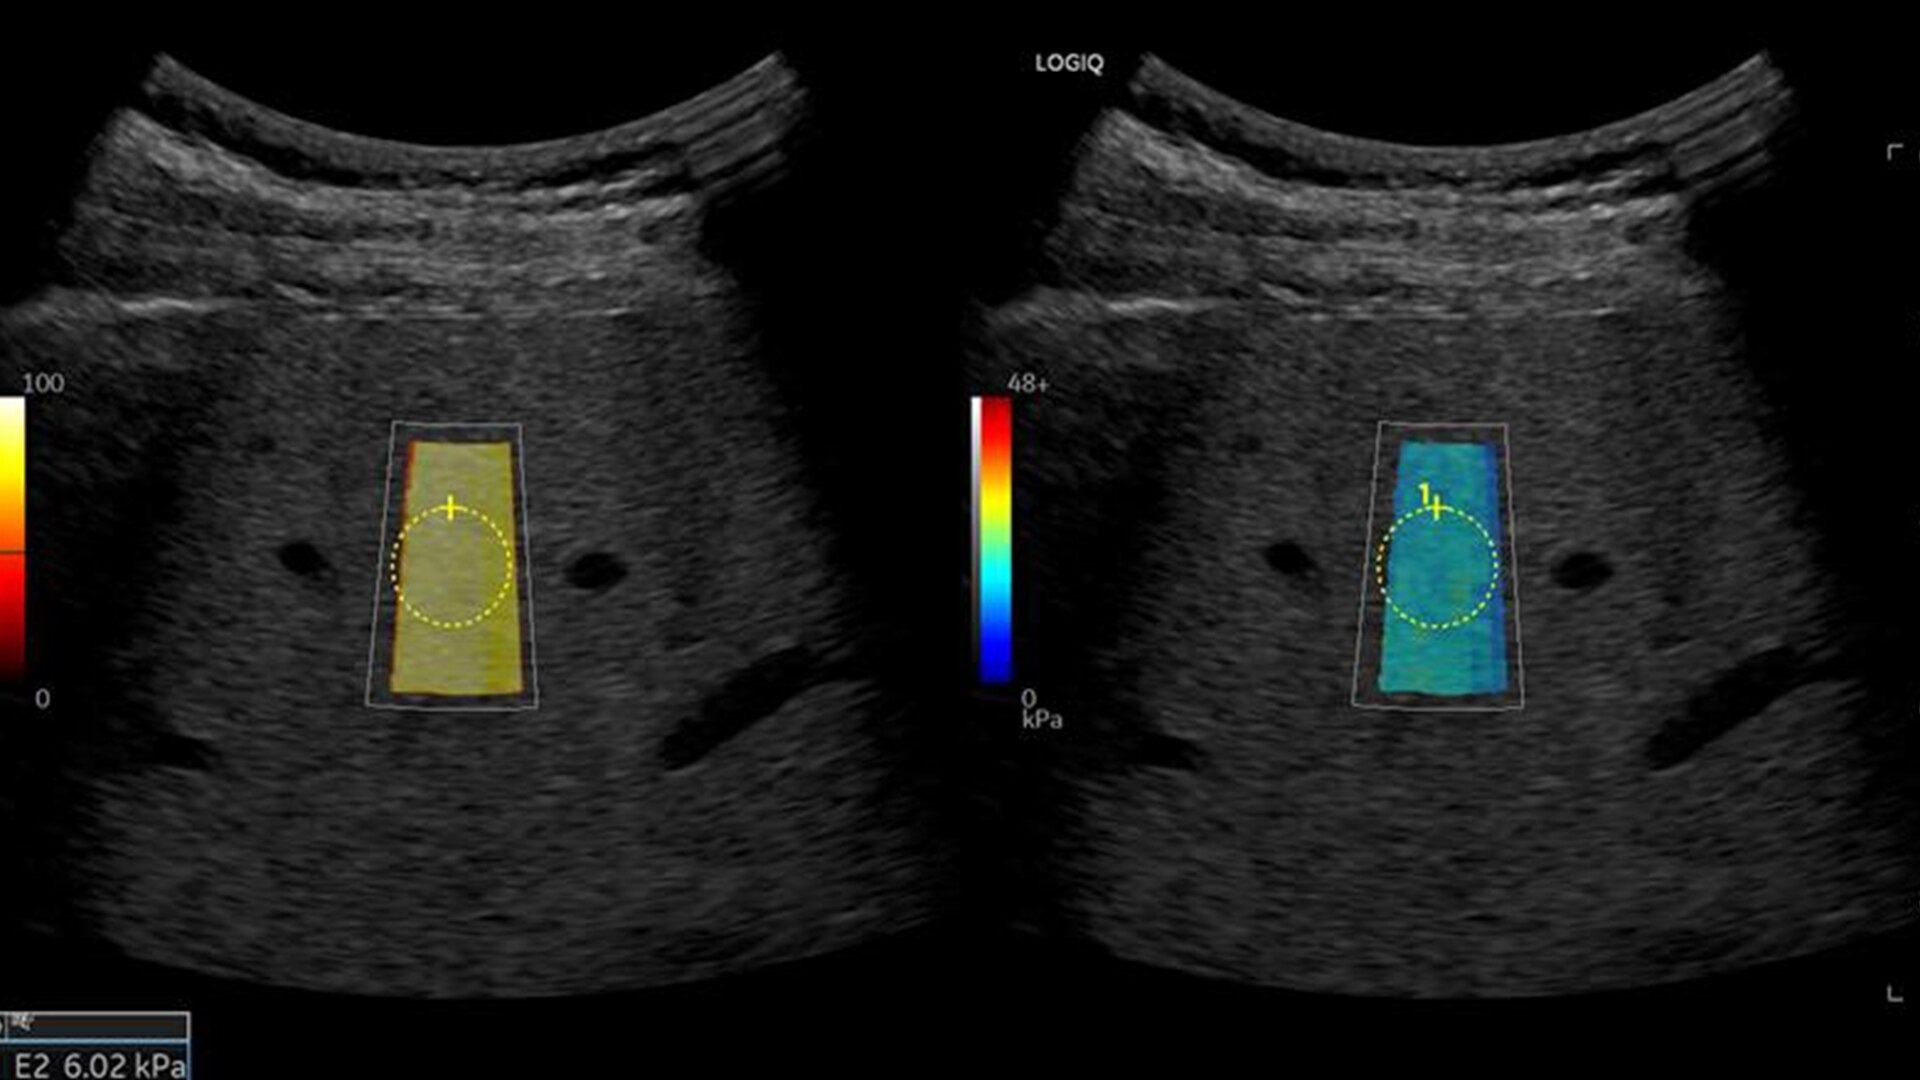

• Ultrasound-Guided Fat Fraction (UGFF) quantifies liver steatosis as a percentage, supporting detection and management - especially for patients with Metabolic Dysfunction-Associated Fatty Liver Disease (MAFLD)

• 2D shear wave elastography with quality map provides quantitative insight into tissue elasticity—helping you assess different structures with confidence

• Hepatic Assistant: Combines 2D shear wave elastography and UGFF in a single workflow